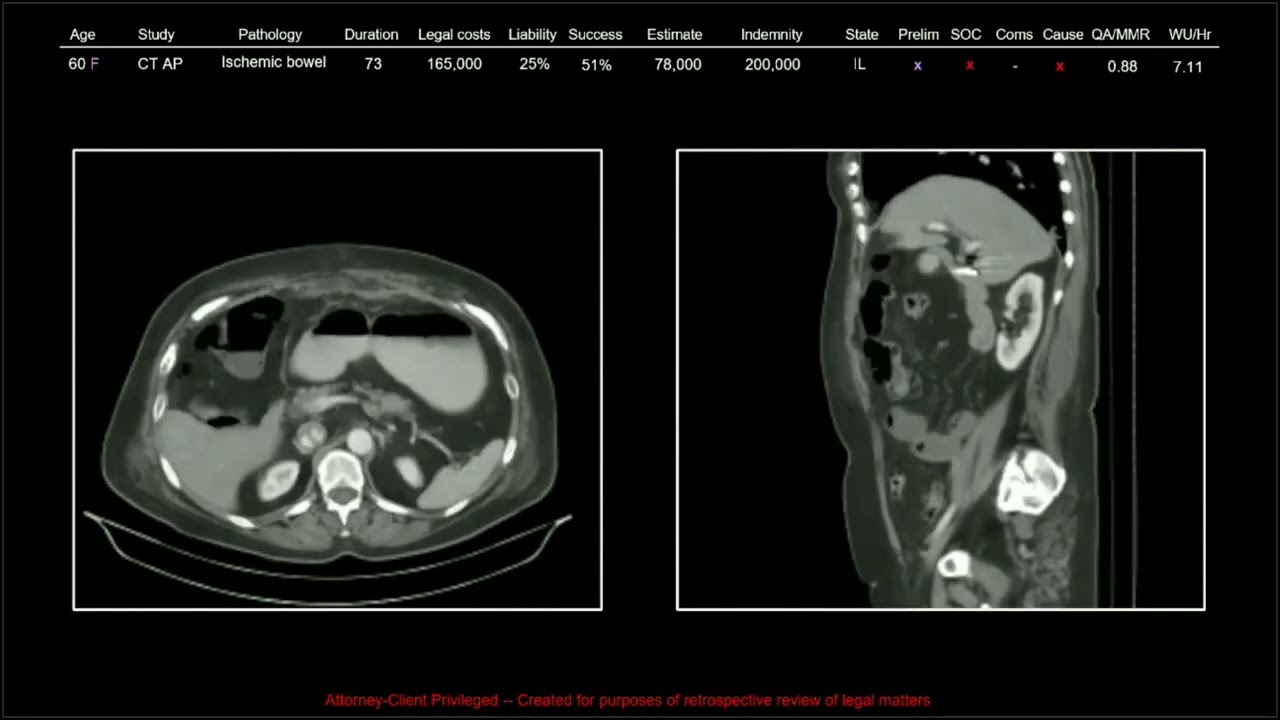

137 Years of Medical Malpractice Part 9 of 9 | Free Radiology CME

1. Understand the importance of aortic, epidural, and superior mesenteric artery evaluations in reducing the risk of medical malpractice lawsuits.